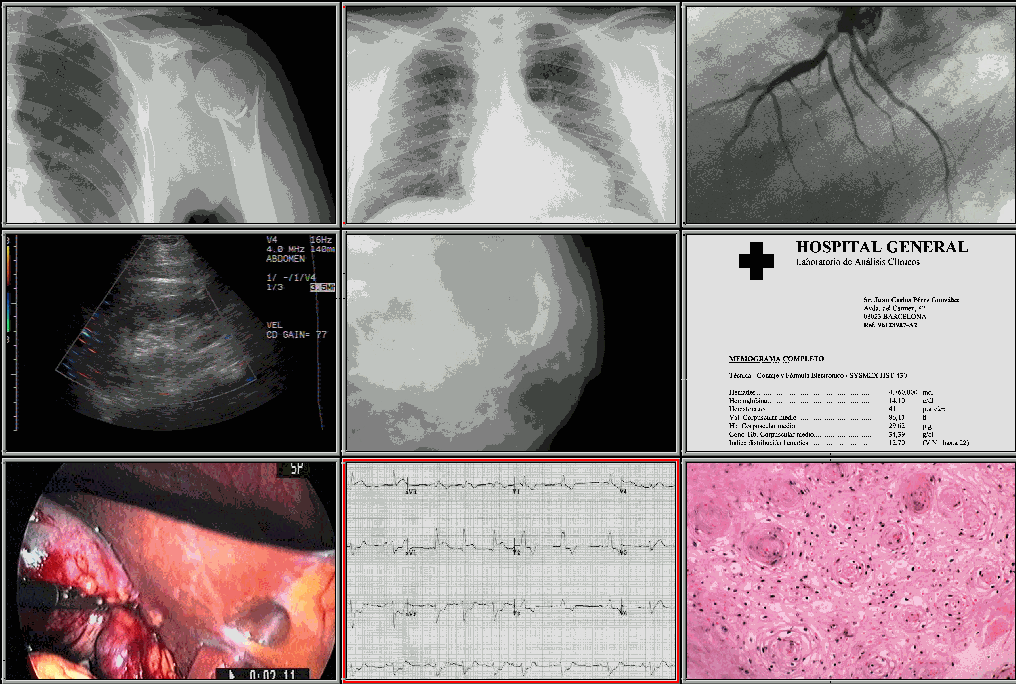

1.- Configuración y Mantenimiento de una Información Sanitaria integrada mediante el uso de arquitecturas de Información que faciliten el acceso pleno a la visualización y explotación de Resultados Médicos multidisciplinares.

Como ejemplos de aplicación se enumeran:

-Configuración de "Motores" de integración para la optimización del enlace entre Atención Primaria y Especializada. El proyecto referido proporciona soluciones para facilitar:

=La coherencia de Datos entre SI (Primaria-Especializada)

=El proceso de Telecita entre áreas

=la devolución a Primaria de los Contenidos resultantes de la práctica especializada (Consultas, Resultados Médicos como Informes, Datos de Laboratorio, Imágenes Médicas, …)

=El Intercambio de Información y opcional Telecompartición "en tiempo real".

y puede convivir en escenarios informáticos y de información heterogéneos.

-Configuración de Redes Globales de Intercomunicación que incluyen procedimientos inalámbricos y tecnologías "portables" ("mobility") que garantizan la accesibilidad a la información desde cualquier escenario. Las áeas de aplicación destacables son:

=La prestación de Cuidados Sanitarios (como Farmacéuticos, Enfermería, Dietética, ...) cuya prescripción y/o consulta podrá realizarse de manera mucho más próxima a los escenarios asistenciales finales

=Herramientas de Gestión (Cuaderno de Mando, …) para el acceso y control, en tiempo real, a o de diversos indicadores asistenciales

Los Proyectos de "Mobility" para la Sanidad integran:

=Dispositivos móviles (PocketPC, TabletPC, …)

=Tecnología de Conexión

=Sistemas de Información

y conectan a los usuarios con los datos clínicos y aplicaciones independientemente del lugar y el momento, posibilitando una mayor dedicación a las tareas asistenciales.

2.- Procedimientos de adquisición, intercambio y compartición de información y documentación sanitaria en redes extensas.

-Proyectos de Telemedicina Documental ejecutados mediante procesos de:

=Intercambio de Documentación Médica Multidepartamental y Multimedia

=Opcional ejecución de procedimientos de trabajo de tipo Consultivo o Compartido (presencial o diferido)

integrados dentro del Curso de Evolución Asistencial Electrónico.

Se aplican a numerosas especialidades médicas y contribuyen, de forma eficaz, a la interconsulta entre áreas básicas y atención especializada.